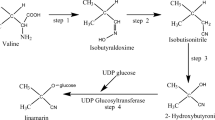

Plant and human aquaporin homology

Vaishnav and colleagues [26] did an elegant job of identifying the shared amino acid sequences of human and plant AQPs. Corn (maize), soybean, spinach leaf, and tomato AQPs have homology to AQP4 (Fig. 1). Shared structural homology between dietary proteins and human tissues can result in autoimmune reactivity in genetically susceptible individuals. Due to a similarity in structure, if antibodies are produced against a dietary protein, such as spinach leaf AQP, those spinach leaf AQP antibodies could potentially mistake AQP4 in the astrocytes for spinach leaf AQP. This mechanism of cross-reactivity, instigated by a dietary protein, and igniting an attack on self-tissue, as if it were foreign material, is illustrated in Fig. 2.